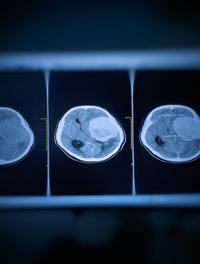

La radiothérapie stéréotaxique corporelle (RSC) consiste en une irradiation tumorale sélective guidée par l’imagerie en temps réel. Elle vise en règle des tumeurs primaires ou secondaires dont les dimensions n’excèdent pas 5 cm, le plus souvent isolées sans envahissement ganglionnaire. Elle permet de délivrer avec une précision millimétrique des rayons X de haute énergie sous la forme de mini-faisceaux multiples, généralement non coplanaires, des doses élevées fractionnées [...]